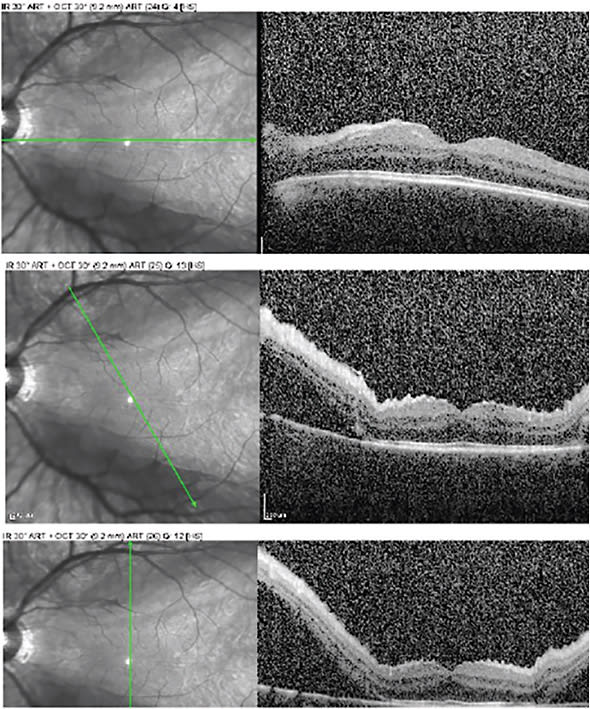

Rhegmatogenous retinal detachments should be considered a surgical urgency; however, this doesn’t apply to all retinal detachments. We’re often asked ‘is the macula on or off?’ but the real key to determining the urgency of a case should be whether or not the fovea is attached. This isn’t always readily apparent clinically, especially when shallow fluid is present. However, OCT imaging enables us to more objectively determine the status of the fovea and/or the extent of macula involvement.

Figure 2 shows what we have termed a “fovea-sparing macula-off” rhegmatogenous retinal detachment. There is evidence that the macula is detached. In addition, the OCT shows subretinal fluid present in the superior and inferior macular area, shallow retinal folds secondary to subretinal fluid, and a high watermark above the fovea, suggesting relative chronicity. However, one can consider this an urgency, because the fovea remains attached and the presenting visual acuity was 20/25 for this patient; consequently, without urgent surgical reattachment, there is significant risk of vision loss.